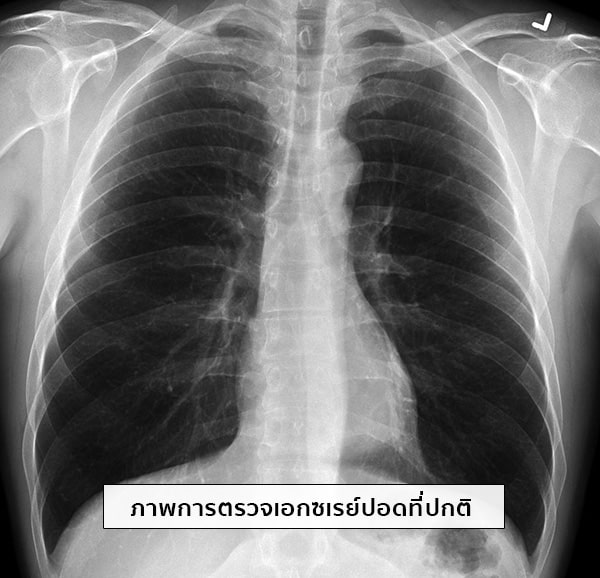

คู่มือการถ่ายภาพเอกซเรย์ เอกซเรย์ คู่มือ หนังสือ RT รังสีเทคนิค รังสี … การตรวจเอกซเรย์ปอด (Chest X-ray : CXR)

การตรวจเอกซเรย์ปอด (Chest X-ray : CXR) รูปหัวใจคู่สีแดงสวยงามพร้อมความรักเล็ก ๆ อยู่ตรงกลาง PNG , สวย, สีแดง …

BRH-MICCAL-Learning: ภาพถ่ายรังสีทรวงอก-การแปลผล-ตรวจสุขภาพ รู้ทัน… ภาวะหัวใจล้มเหลว